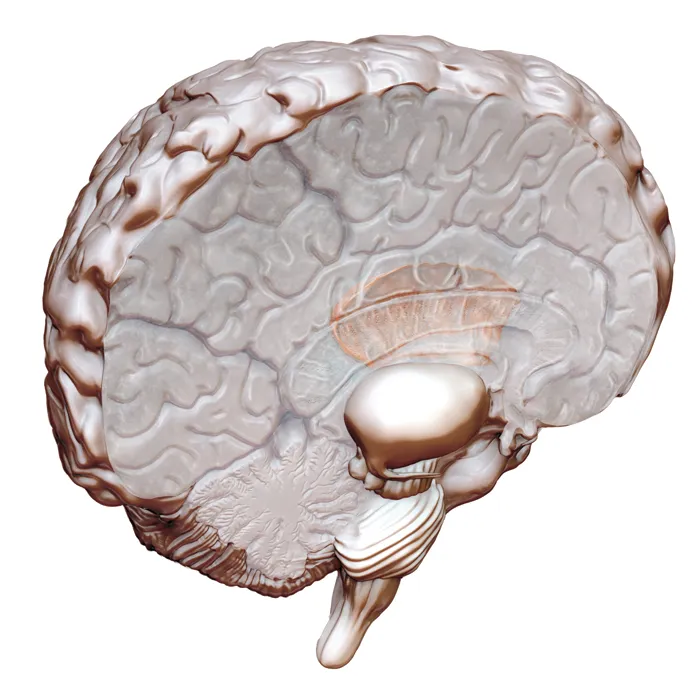

The abrupt switch from awareness to its complete absence may be orchestrated by an enigmatic wisp of brain tissue known as the claustrum, scientists propose June 24 in Epilepsy & Behavior. The consciousness-impairing electrode was positioned close to this thin sheet of cells, which forms connections with many other regions of the brain.